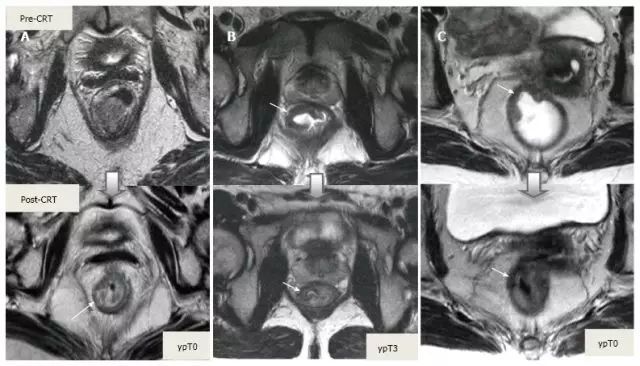

新辅助 CRT 可以降期、缩小肿瘤,减小手术范围,减少局部复发和改善生存。重新分期需比较治疗前后图像所有因素,要尽量保证图像相同条件和层面。

1.T 分期

采用传统 MRI 序列对 CRT 后肿瘤重新分期的精确性差于初始分期,尤其在证实完全缓解(yT0),主要是很难将残留的肿瘤与纤维化、水肿和正常粘膜区分开,因此 CRT 后正常的 2 层直肠壁提示为完全缓解,而残留纤维化既可以是肿瘤残留也可以是完全缓解(图 17)。

实际上 CRT 后 T2 加权 MRI 后上纤维化的信号强度很低,而残留肿瘤区域则为中等强度,仔细评估高分辨图像和 DWI 是能区分小的残留病变和纤维化的(图 18)。

图片

图 17. 新辅助放化疗后肿瘤重新分期。在不同患者的 T2 加权 MR 图像上分别显示(上:治疗前,下:治疗后)。A. 在 ypT0 直肠肿瘤中,治疗后的轴位图像显示正常的两层直肠壁(箭头),对应完全缓解;B. 在 ypT3 直肠肿瘤中,治疗后的轴位图像显示正常的双层直肠壁(箭头)。这是 MR 评估完全缓解的假阴性例子;C. 在 ypT0 直肠肿瘤中,原有肿瘤区域治疗后呈现厚的、纤维化的低信号强度疤痕(箭头)。